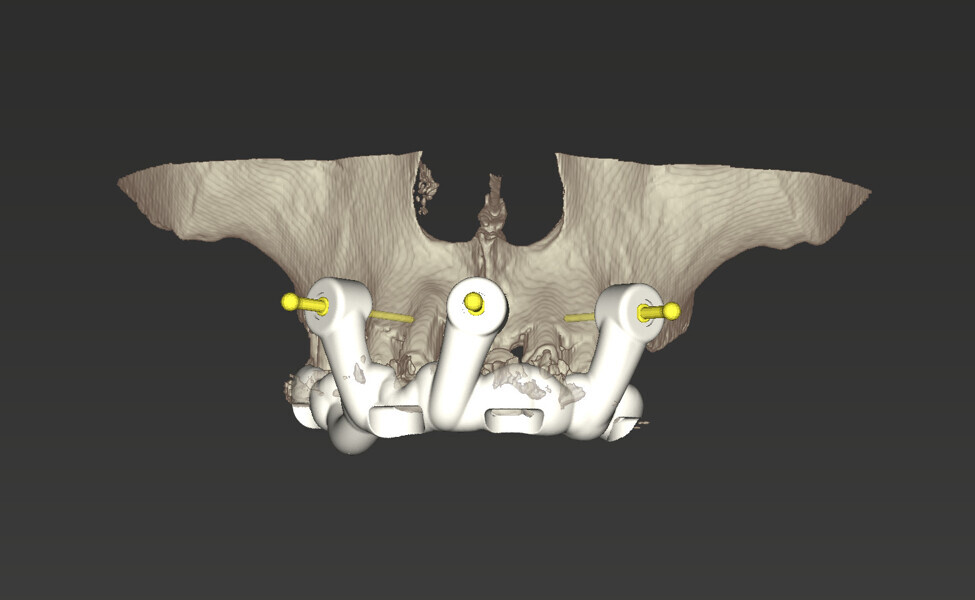

Compromised maxillary dentition treated with Straumann Pro Arch and a digital workflow